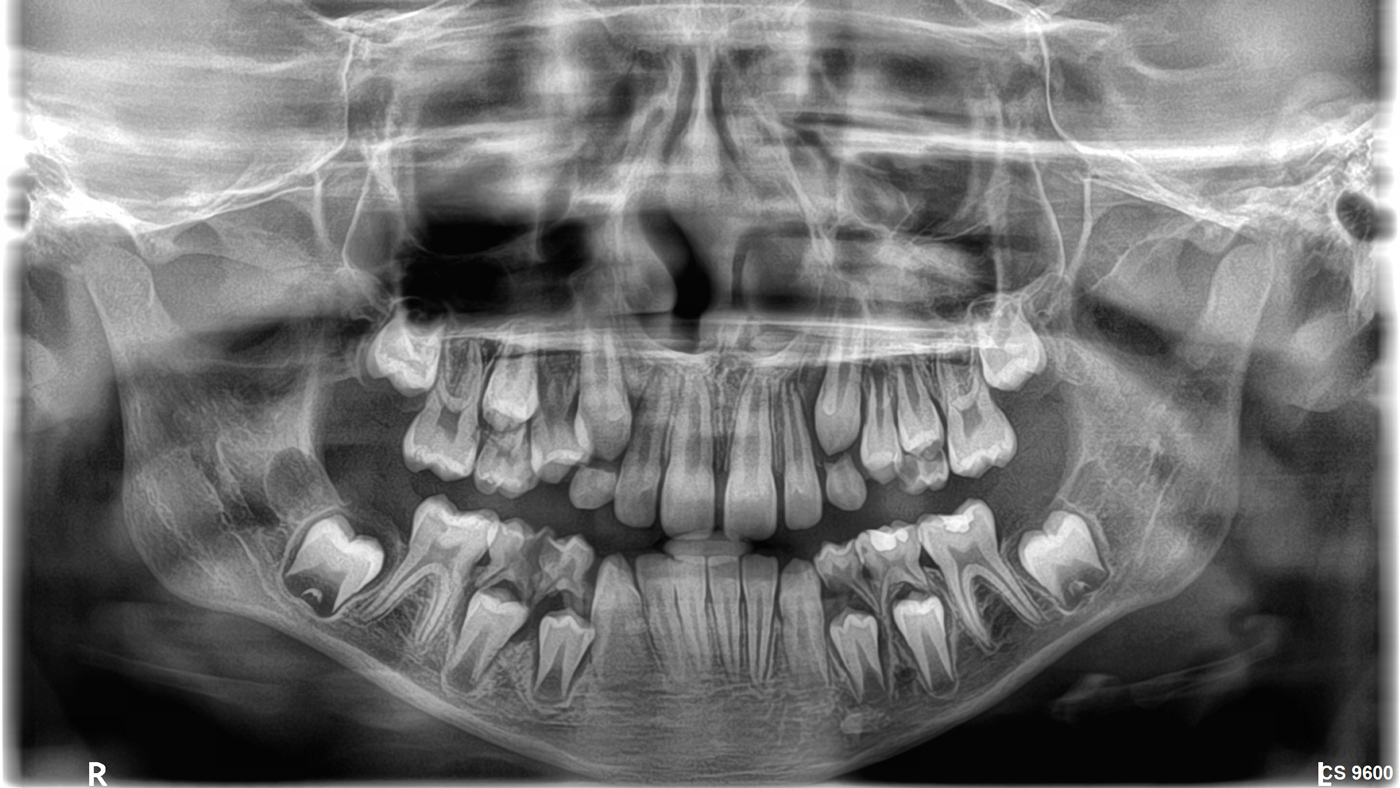

- Άριστη ψηφιακή Πανοραμική ακτινογραφία (2D).